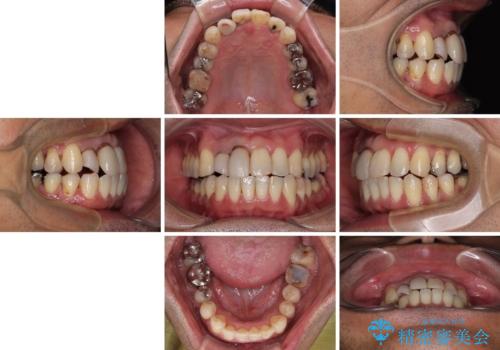

隠れている前歯 インビザライン矯正治療と前歯のセラミック治療

- 隠れるほどに内側に転位しいてる前歯を気にして来院された患者様です。

仕事柄海外出張が多いとのことで、インビザラインにて矯正治療を行うこととしました。

矯正治療後は、前歯や下顎の奥歯など、むし歯治療途中の歯をオールセラミッククラウンにて補綴治療を行うこととしました。

治療途中で海外に長期滞在することとなり、5年近く帰国することができなかったため、治療期間は非常に長いものとなりました。

内側に転位していた前歯は、矯正治療では治しきることができませんでしたが、幸いにもオールセラミッククラウンに置き換える予定であったため、希望通りの仕上がりとなりました。